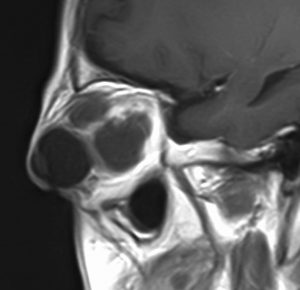

幼児の視路の毛様粘液性星細胞腫です。T2強調画像(左側)で白く高信号に写るのが特徴です。ガドリニウム増強ではまだらになっていますが,均一に真っ白に高信号になることも多いです。乳幼児のものは,ドロドロに柔らかい腫瘍です。